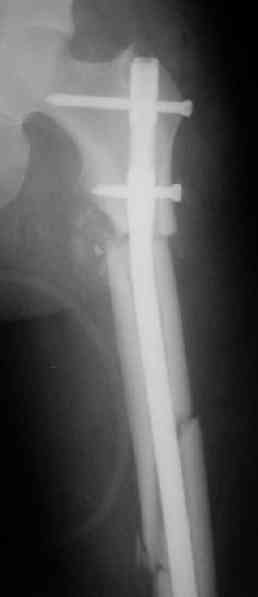

СМ> Что, реально изогнуть титановый гвоздь, не сломав его?

Конечно. Чтобы не сломать, лучше проложить в тиски сразу ниже отверстий полоску металла, чтобы там создалась концентрация напряжений при изгибе, а не на уровне отверстия.

СМ> Если имеются под рукой Р-снимки, продемонстрируйте, плиз.

Вот несколько. С тисками и трубой на днях сделаем.